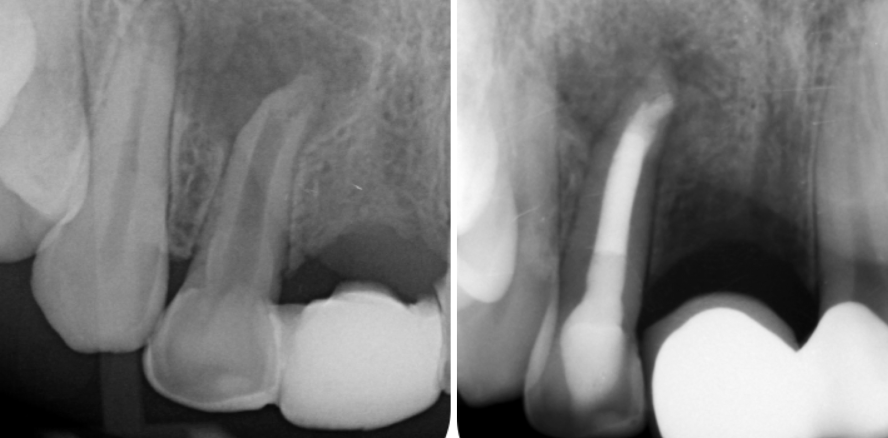

Zuverlässig auf die Arbeitslänge zu kommen und enge, gekrümmte oder sehr lange Wurzelkanäle sicher aufbereiten zu können. Der folgende Artikel soll...

Zuverlässig auf die Arbeitslänge zu kommen und enge, gekrümmte oder sehr lange Wurzelkanäle...

In diesem Beitrag werden die Relevanz und Erkenntnisse klinisch etablierter sowie experimenteller Möglichkeiten der Bildgebung für die zahlreichen Variationen...

In diesem Beitrag werden die Relevanz und Erkenntnisse klinisch etablierter sowie experimenteller...